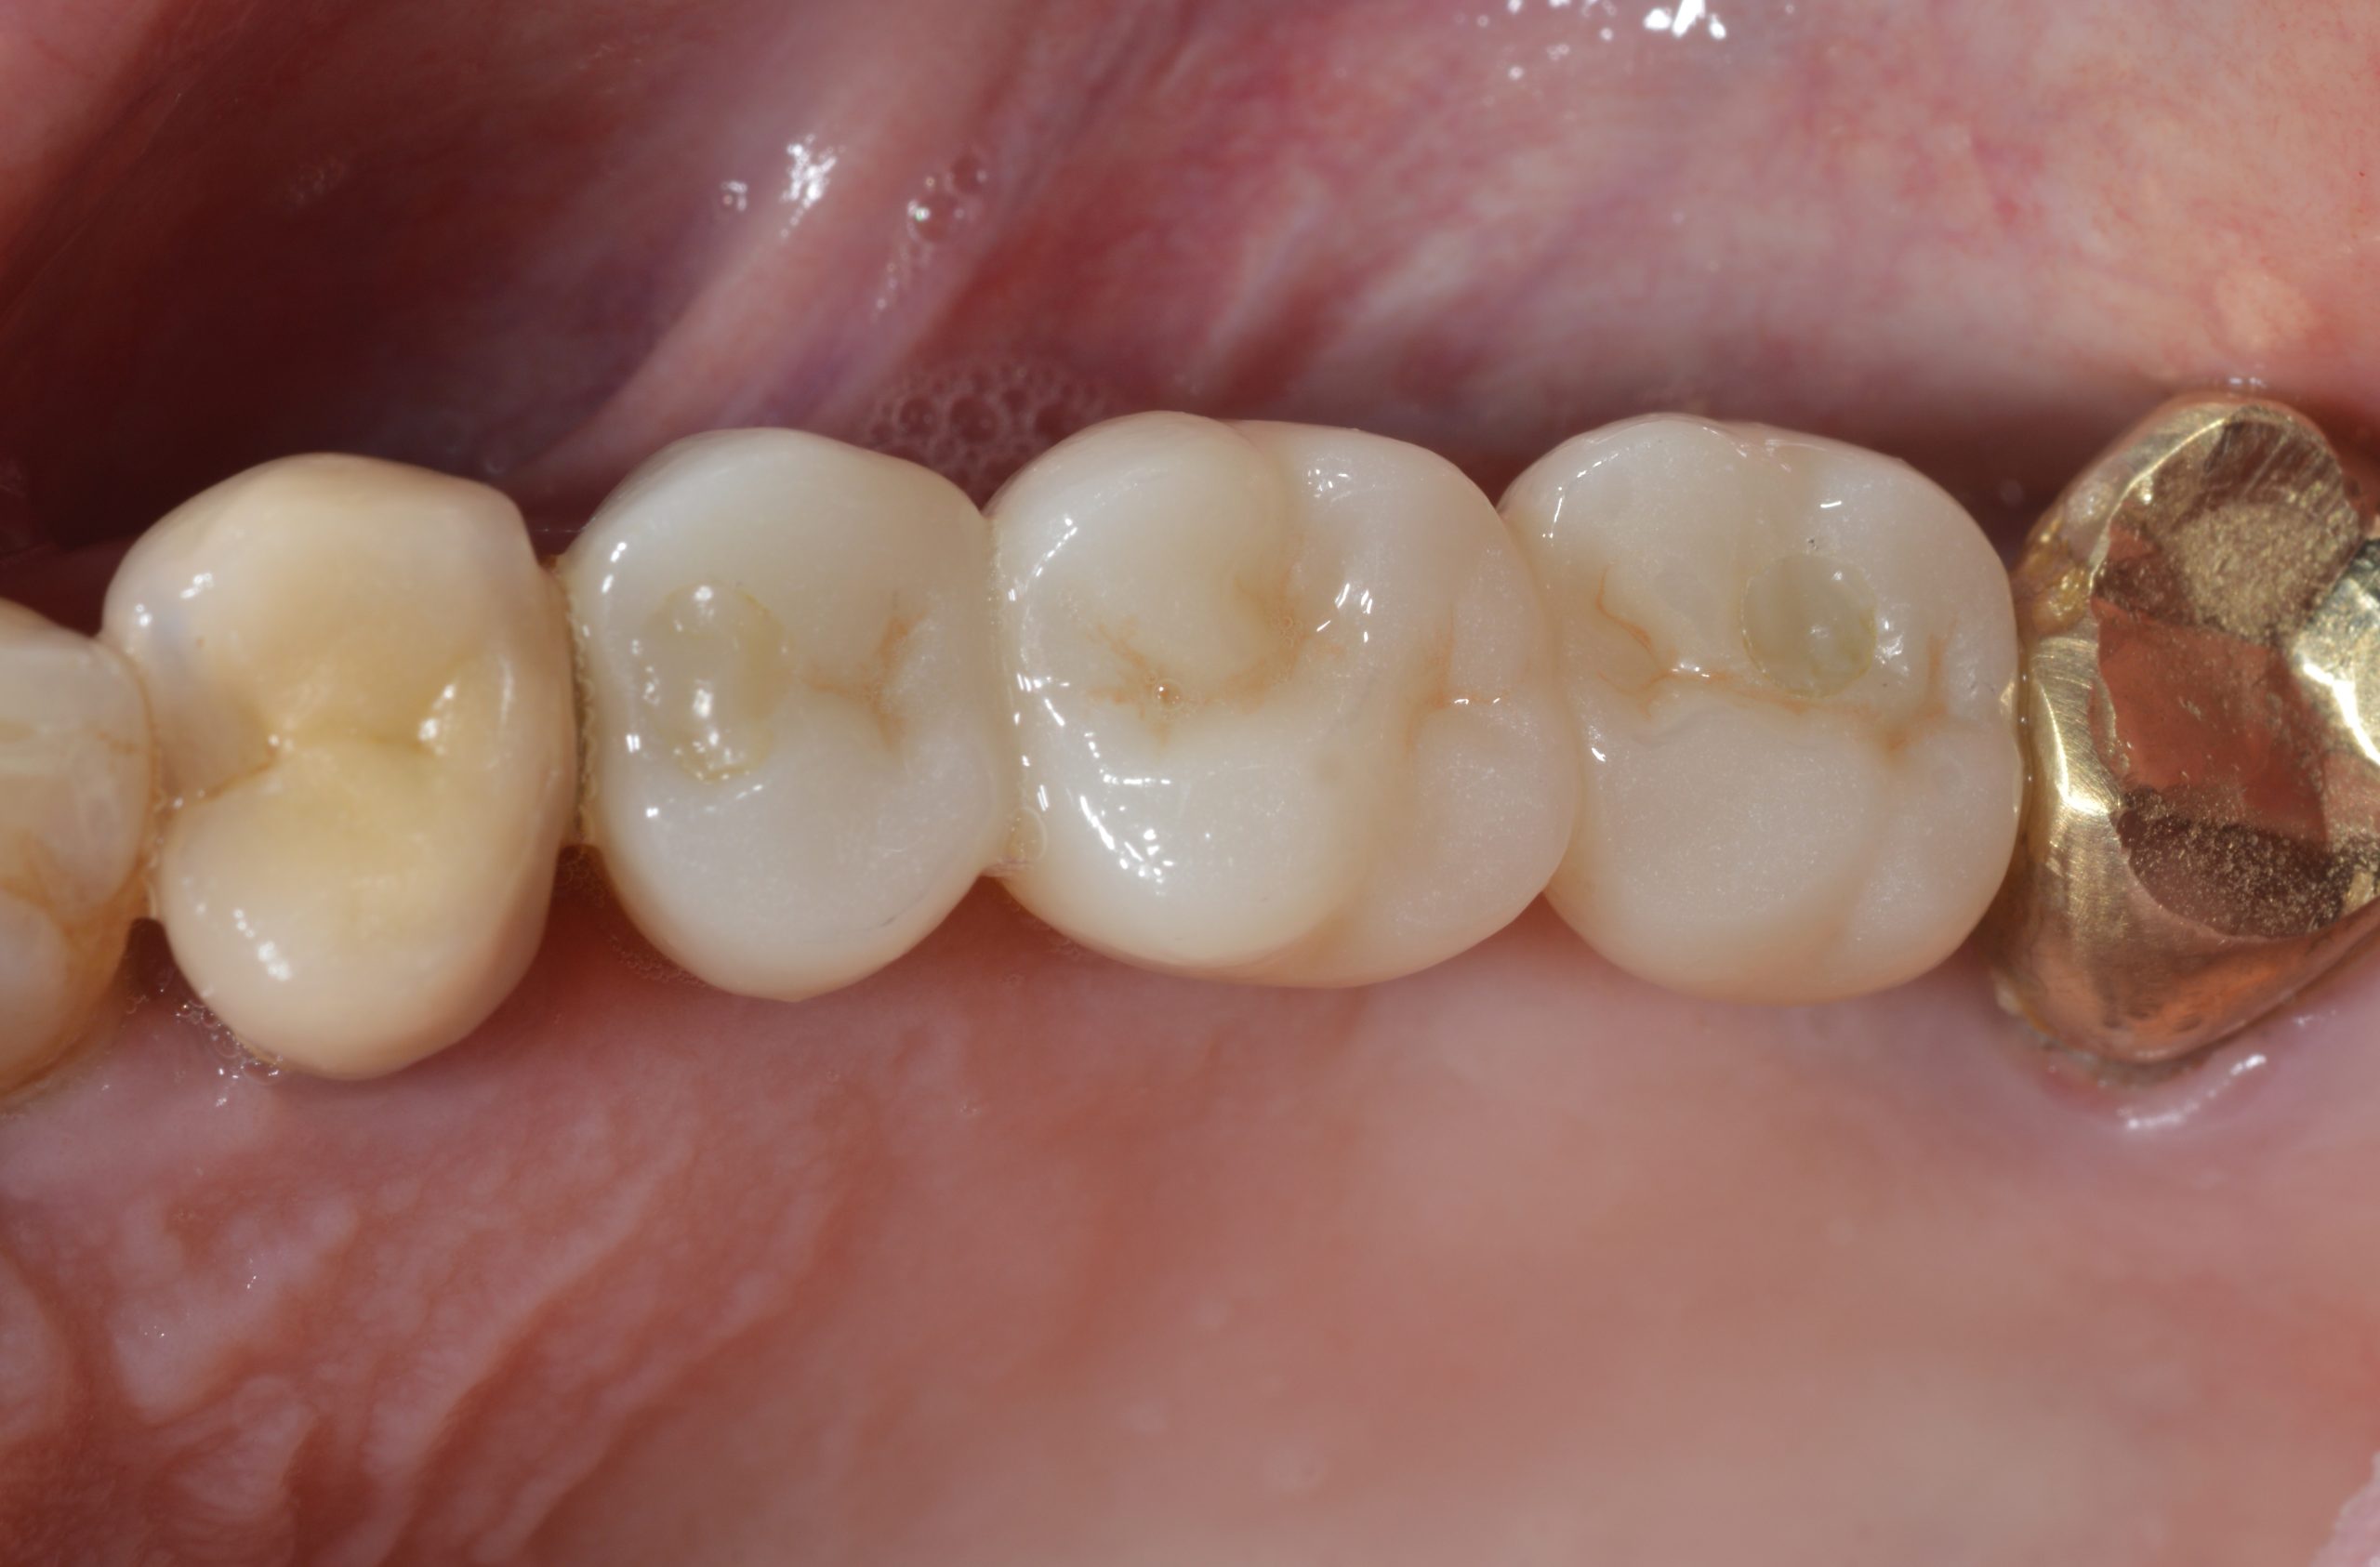

Excellent fit and functional as well as highly esthetic result. The final prosthesis was placed five months after implant placement. The occlusal screw openings were “service-friendly” sealed with composite.

Good soft tissue stability is also evident 23 months after implant placement. Satisfactory cleaning also contributes to this.